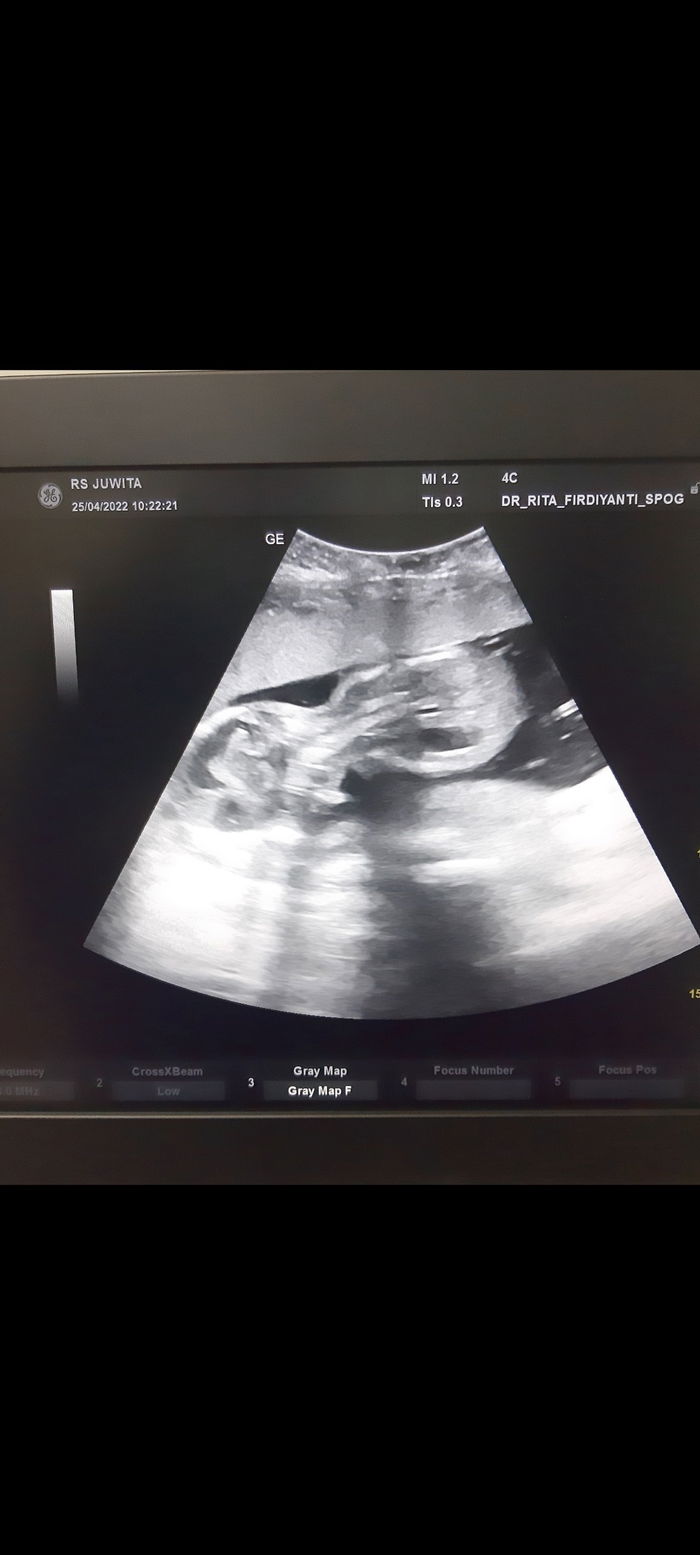

Februari – Juli 2022, tak disangka tak dinyana, kehamilan keduaku mirip dengan kehamilan pertamaku, aku mengalami morning sickness yang meningkat menjadi hiperemesis. Mual dan muntah yang biasanya hanya datang saat pagi hari saja ternyata terus berkepanjangan sampai waktunya tidur. Lemas rasanya yang aku rasakan setiap harinya. Namun, perlahan-lahan rasa mual dan muntah itu mulai mereda disaat usia kehamilanku 25 minggu. Alhamdulillah sejauh ini, kandunganku sehat dan tumbuh optimal sesuai dengan usianya.

Agustus 2022, wow sekali bulan Agustus ini, perasaan semakin tidak karuan karena bulan depan si baby akan lahir ke dunia. Dibulan ini ada hal yang tak disangka terjadi padaku, sebagian orang berpikir mungkin ini penyakit biasa saja nanti pun sembuh. Tahukah parents apa yang terjadi padaku? Aku terkena diare akut. Sebagian orang beranggapan ini suatu penyakit yang tidak berbahaya. Hmm, tapi ternyata berbahaya untuk ibu hamil. Bagaimana tidak? Janin yang ada didalam perutku seperti tidak nyaman. Aku merasakan yang namanya kontraksi, kontraksi yang mana tidak pernah aku rasa sebelumnya. Malam itu juga aku dilarikan ke UGD salah satu Rumah Sakit tempatku tinggal. Wow, aku terheran dan terdiam saat sampai bukan aku yang dicek lebih dahulu (maksudnya bukan aku yang diobservasi dulu, tapi lebih fokus ke janin dalam kandungan). Sakit sekali kontraksi saat itu, dilakukan pengecekkan CTG detak jantung janin masih normal semuanya. Aku lega sekali. Allahmdulillah yaAllah.. Keesokan harinya, cek bersama dokter obgyn ku, ternyata karena kontraksi yang tiada hentinya, dokter menyarankan agar disuntik pematangan paru, dengan alasan dikhawatirkan aku akan melahirkan bayi yang belum cukup bulan. Detik itu juga, aku sangat cemas sekali. Aku takut jika terjadi hal-hal yang tidak aku inginkan. Cukup 3hari aku dirawat. Tubuhku akhirnya memberikan sinyal yang nyaman. Tetapi ini tidak bertahan lama, karena beberapa minggu kemudian aku merasakan kontraksi palsu yang tidak lazim.